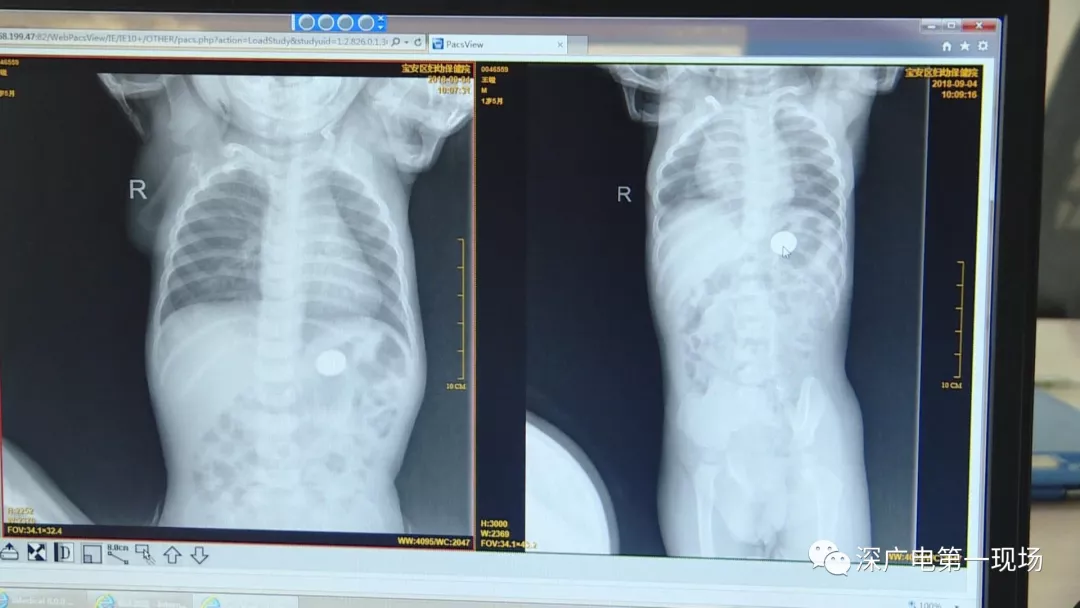

細(xì)心的醫(yī)生竟從

孩子的胸片中有了意外發(fā)現(xiàn)

9月4號(hào),一名1歲零5個(gè)月的男嬰因在家中摔傷,被父母送到了寶安區(qū)婦幼保健院,醫(yī)生診斷為左側(cè)尺橈骨骨折。在進(jìn)行全麻手術(shù)之前,院方例行對(duì)嬰兒進(jìn)行了周身檢查。手術(shù)前,兒外科醫(yī)生趙冠聰在查看患者的胸片時(shí),發(fā)現(xiàn)這名嬰兒的胃部有一枚硬幣大小的暗影。

胃部取出一角硬幣

已吞咽半月之久

經(jīng)過(guò)兩個(gè)小時(shí)的時(shí)間,兒科醫(yī)生郭景濤為患兒取出了藏在胃底的一角錢(qián)硬幣。目前,患兒已經(jīng)痊愈出院。